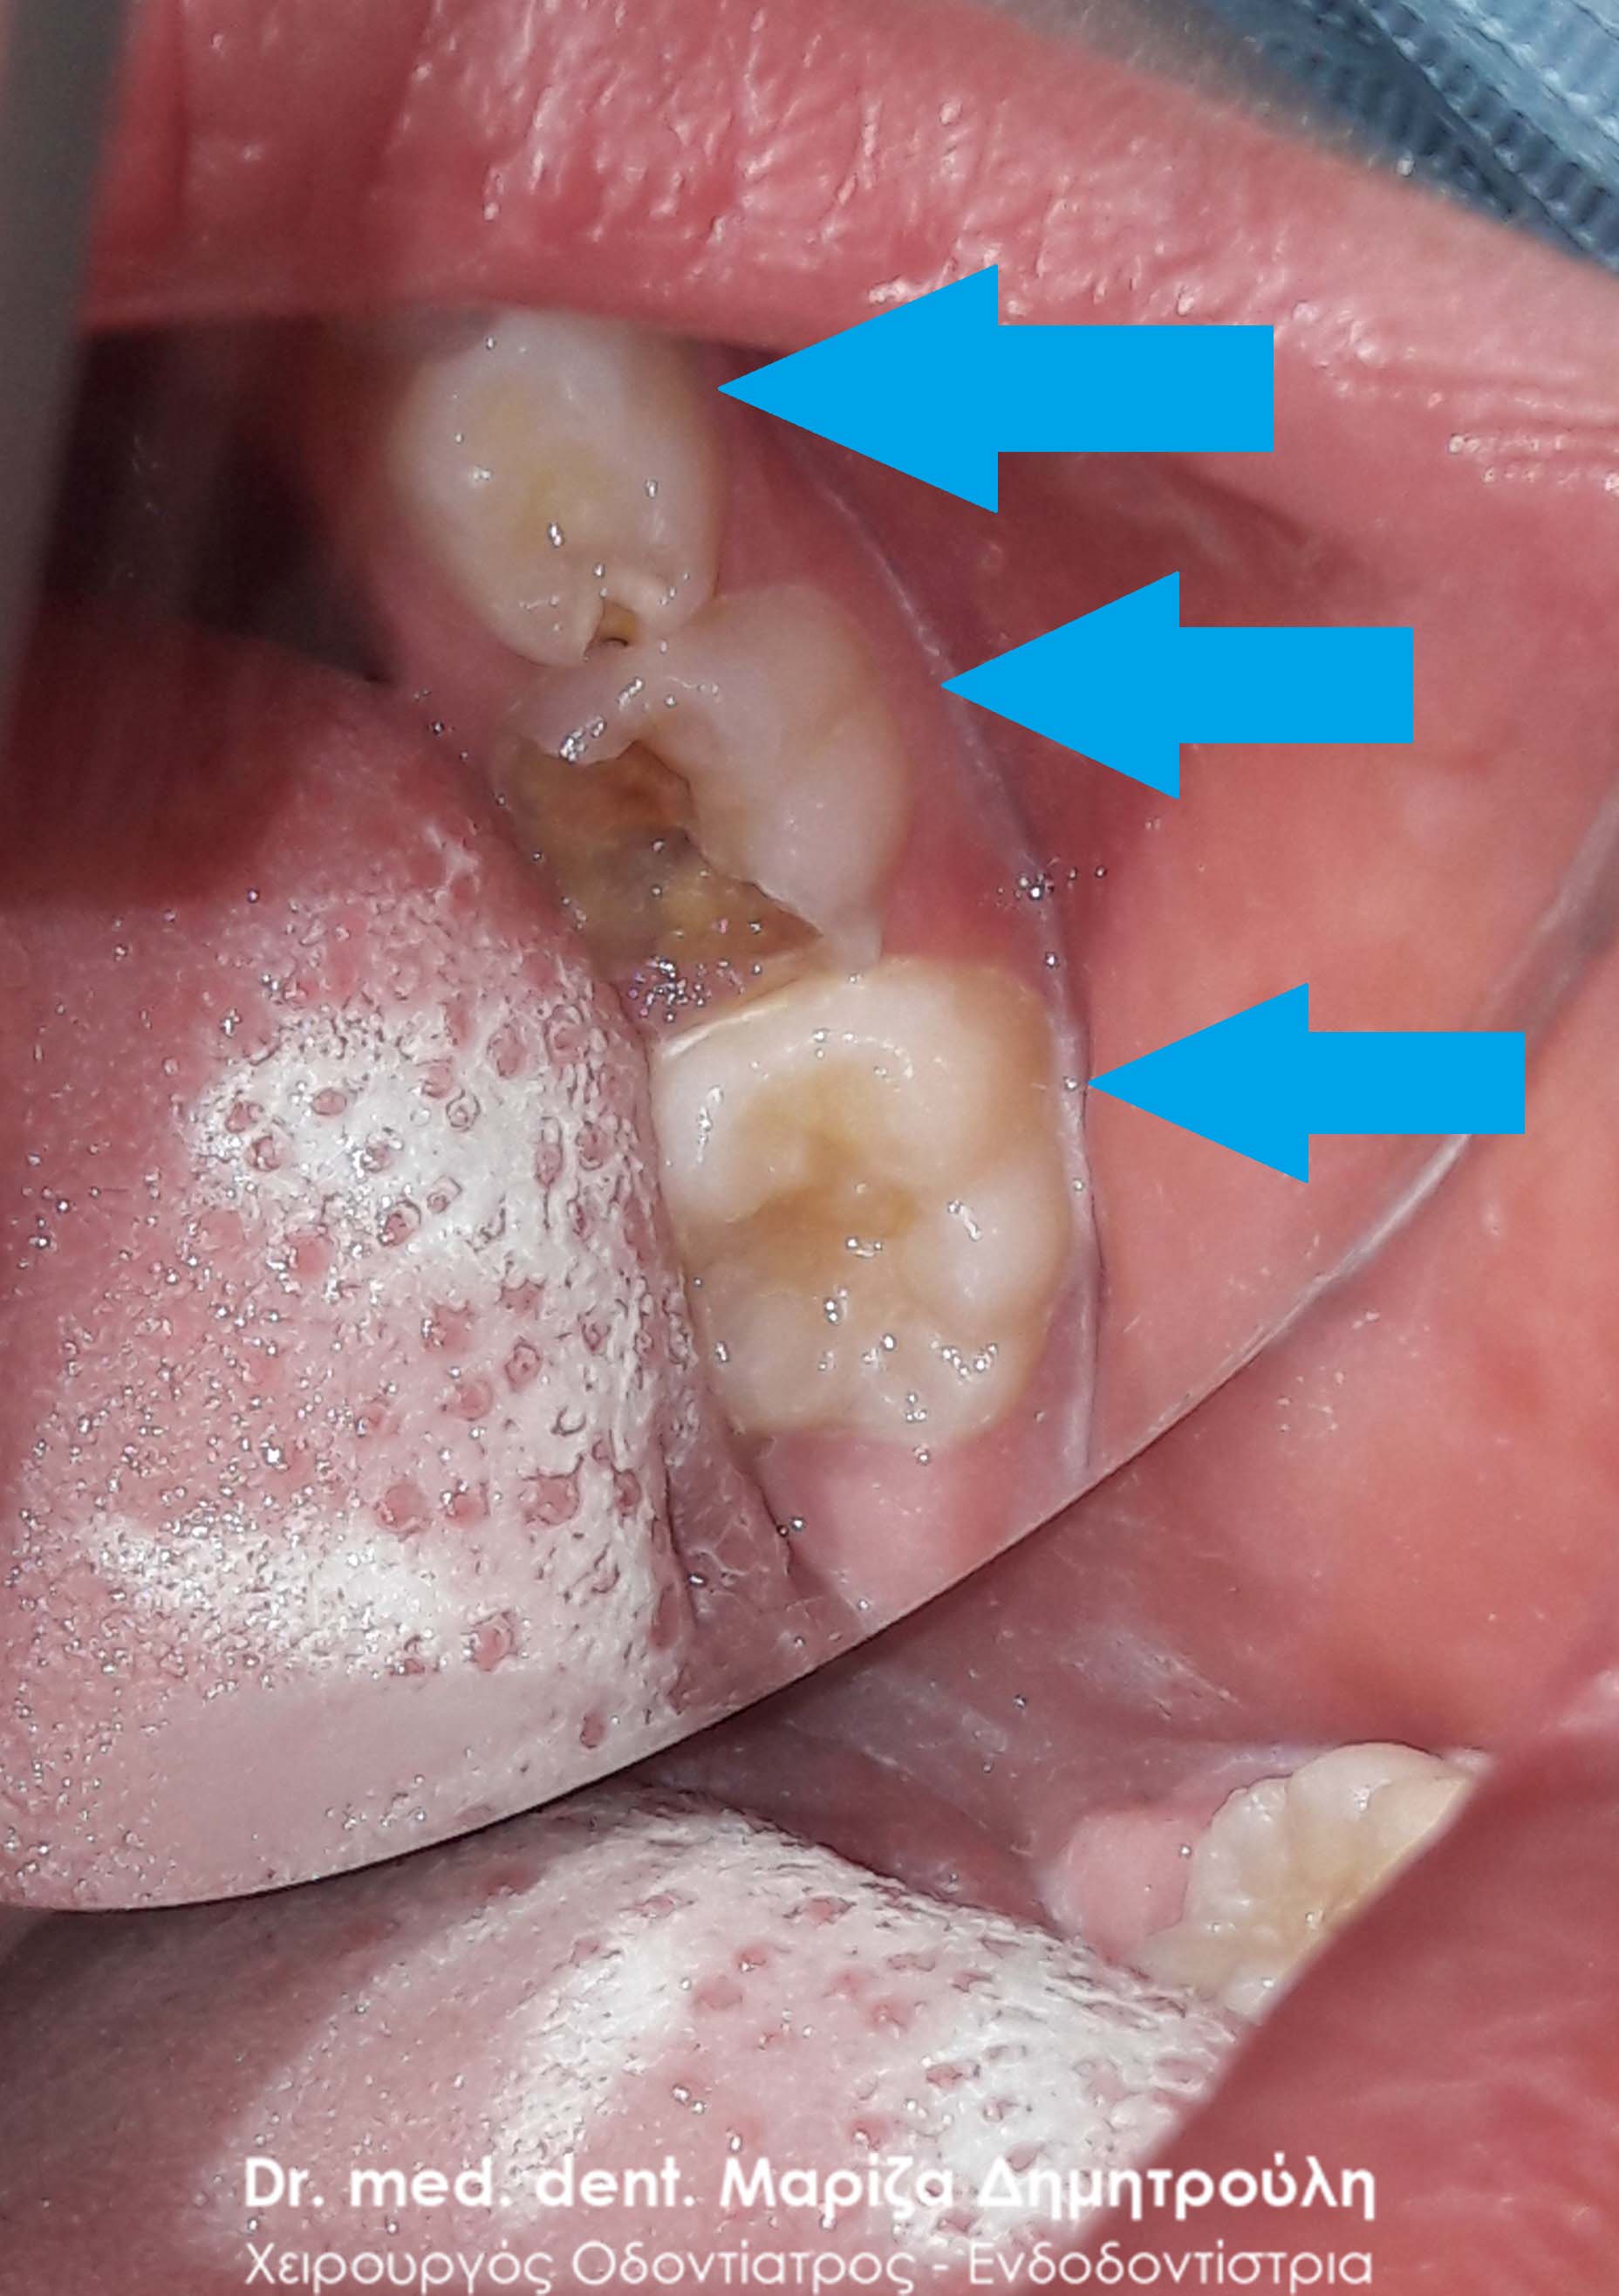

Ο ασθενής παραπονιόταν για πόνο κατά τη μάσηση στη πάνω δεξιά πλευρά του. Μετά την κλινική εξέταση διαπιστώθηκε η ύπαρξη 2 δοντιών με βαθιά και εκτεταμένη τερηδόνα. Μετά την απομάκρυνση της τερηδόνας πραγματοποιήθηκαν λευκά σφραγίσματα σύνθετης ρητίνης.

ΠΡΙΝ

ΜΕΤΑ